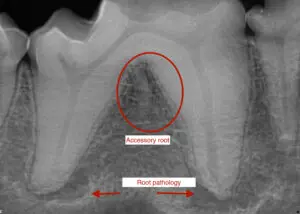

Below is an image from a Diplomate friend of mine (Jean Battig in Portland, OR) of a diseased mandibular 1st molar with an accessory root. This tooth must be surgically removed vs having a root canal therapy.

Take home message: Many two-rooted teeth may have accessory roots. Sometimes, these teeth have problems, so knowing the root anatomy makes it much easier to extract. Without X-rays, you will leave a diseased root in the mouth that can cause continued oral pain.